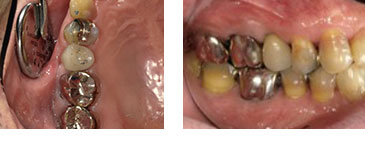

右上5番歯根破折 抜歯即時インプラント埋入

BEFORE

AFTER

| 金額 | ¥460,000(税抜) |

| 期間 | 約3ヶ月 |

| リスク | オペから6週までは過大な力がかかると骨の2次安定が得られないことがあるため、注意を要する。 |